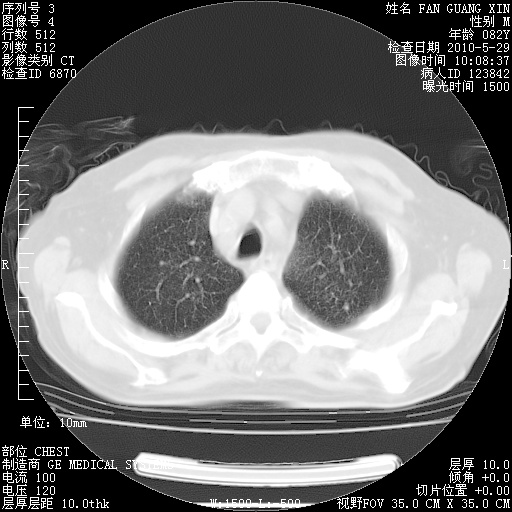

再治疗10天后的肺部CT